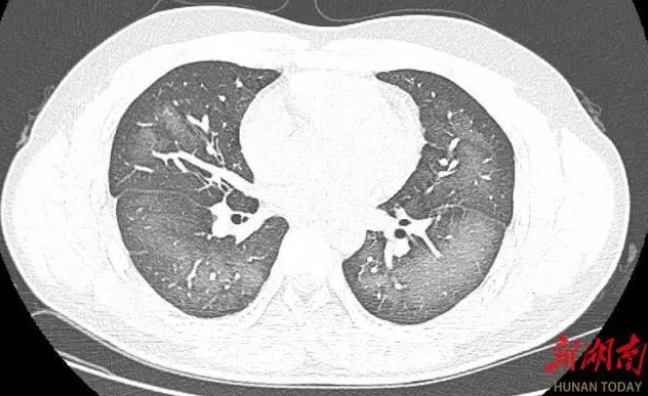

经检查,肺部CT片显示,李林双肺赫然呈现大范围白色样病变,报告提示“白肺”。

长沙市第三医院放射影像科的接诊医师表示,除了感染、弥漫性肺泡出血综合征等“白肺”最常见的病因外,吸入有害物质如粉尘、喷雾等,也可导致肺部出现大范围白色样病变。这位年轻的患者就是因为使用不当,吸入了一部分防晒产品进入肺部,导致“白肺”的发生。急诊医生给予吸氧、化痰、抗感染等相关治疗后,李林症状得到明显改善。